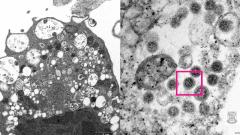

Университет Гонконга на своем сайте опубликовал изображение омикрон-штамма коронавируса, полученное с помощью электронного микроскопа.

На электронной микрофотографии показана почечная клетка обезьяны после заражения «Омикроном». На снимке с сильным увеличением видно поврежденную клетку с набухшими везикулами, содержащими маленькие черные вирусные частицы с шипами в форме короны.